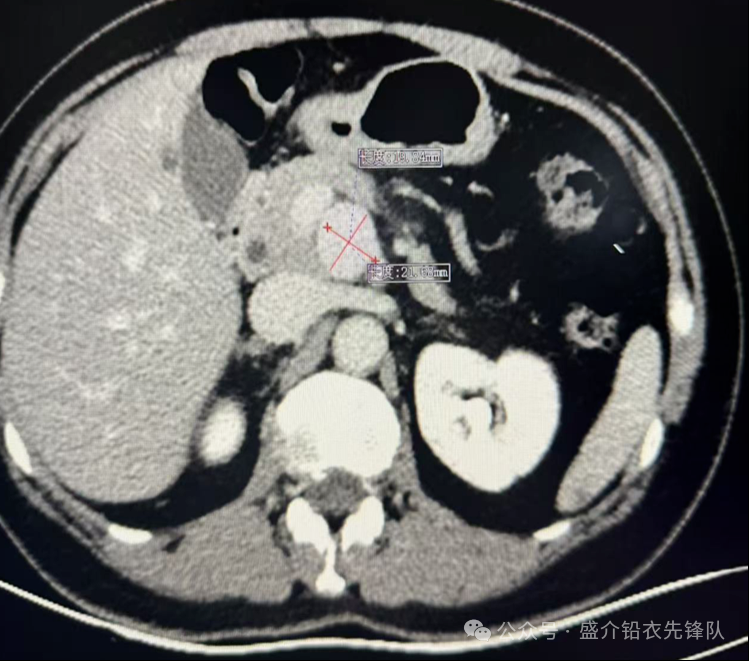

中年女性患者,乳腺癌切除术后复查。发现脾动脉瘤1年。增强CT可见:胰腺颈部后方软组织密度结节,增强动脉期明显强化。大小约:24mm×20mm,与肠系膜上动脉相连接。